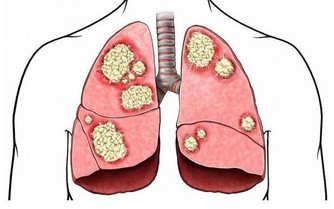

只是作為全身性的疾病,過敏的表現往往不一樣,有人的過敏體現在呼吸道上,就是過敏性鼻炎、過敏性氣管炎、哮喘;過敏體現在皮膚上,則可能表現為濕疹。